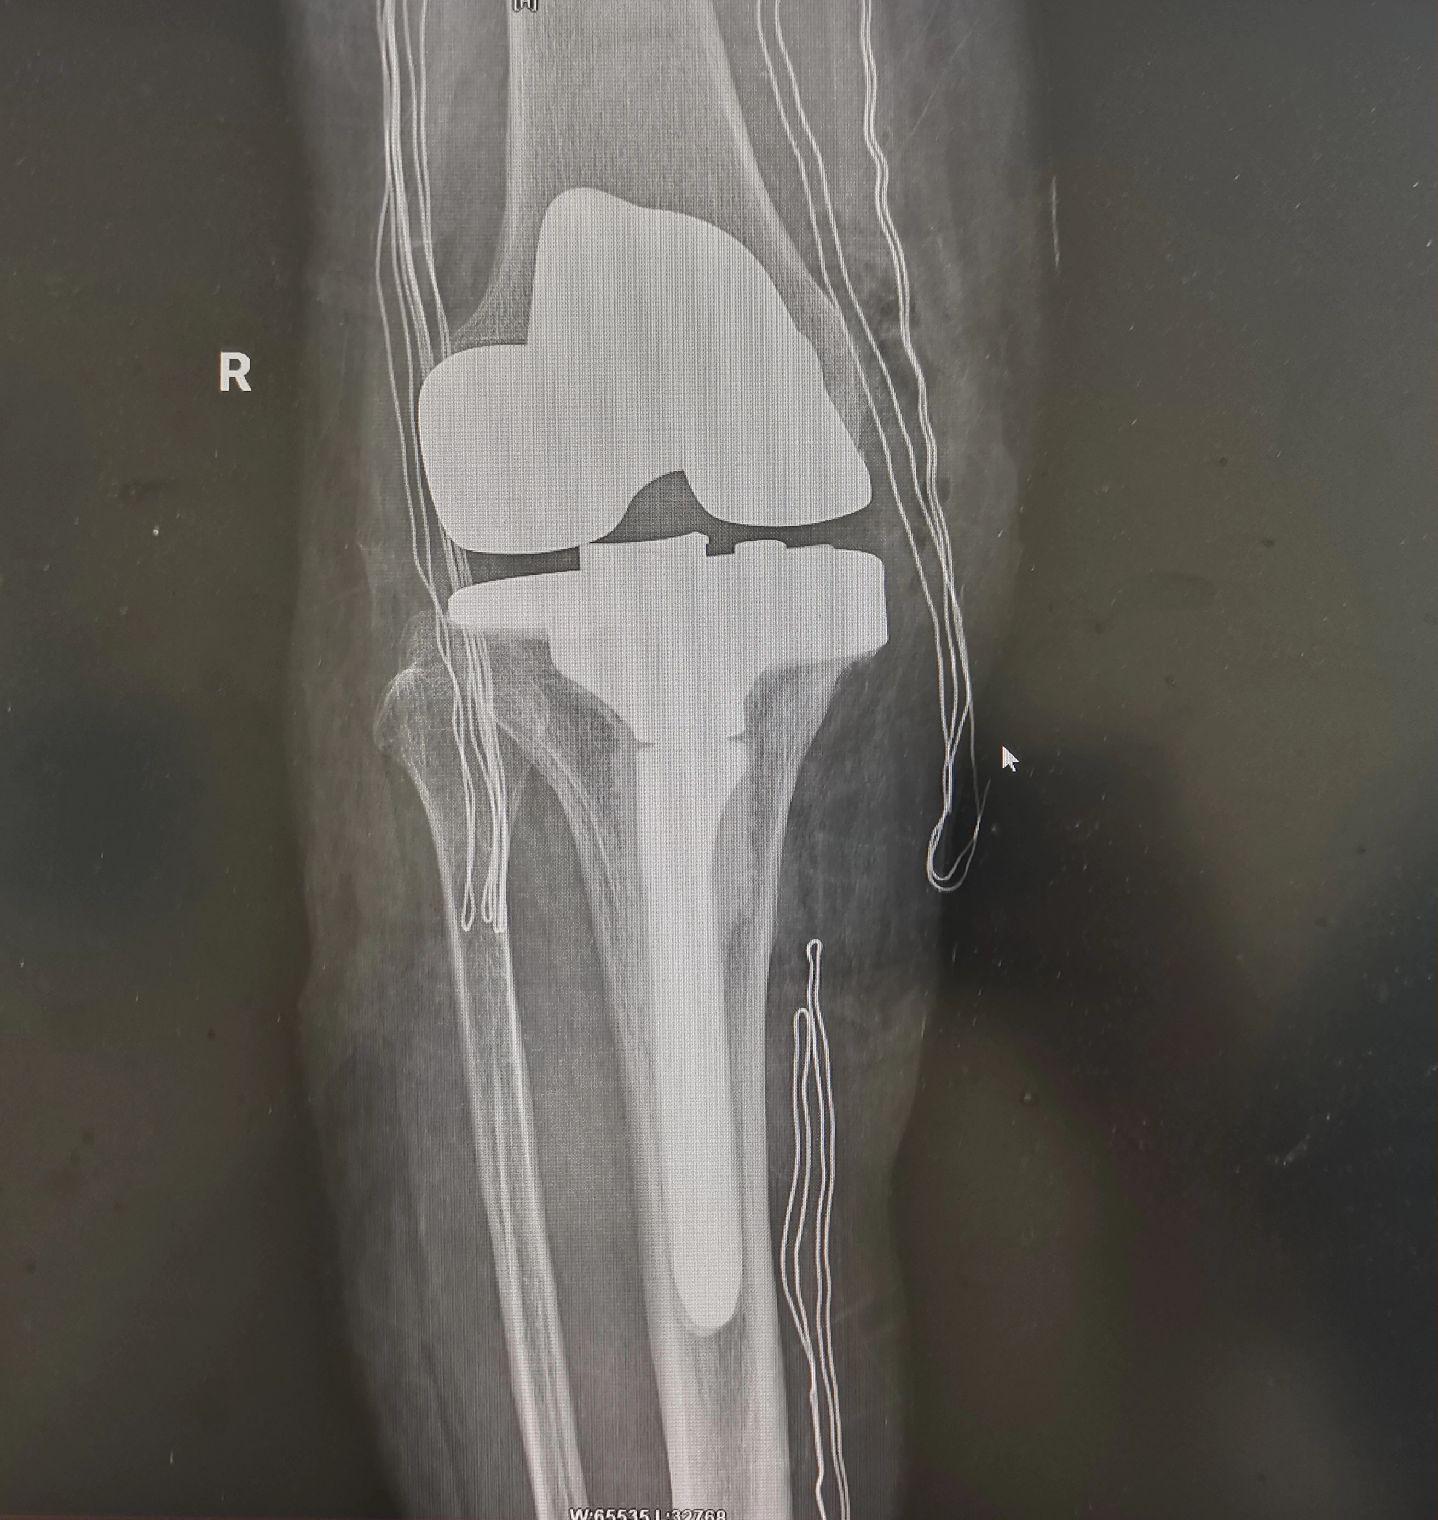

类风湿关节炎。类风湿关节炎,关节毁损,无法行走。备的CCK和铰链膝,最...